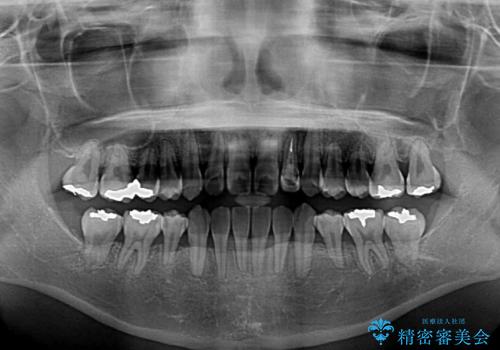

- 下顎の歯が舌側に倒れていることと、前歯の咬み合わせの不具合を気にして来院された患者様です。

受け口傾向の口元であるため、下顎左右小臼歯各1歯を抜歯して歯列を整えることとしました。

前歯には治療中の仮歯が装着されていたため、矯正治療後にオールセラミッククラウンにて補綴治療を行うこととしました。

抜歯矯正は2年から2年半程度の治療期間を要することが一般的ですが、僅か1年1ヶ月で終了しました。